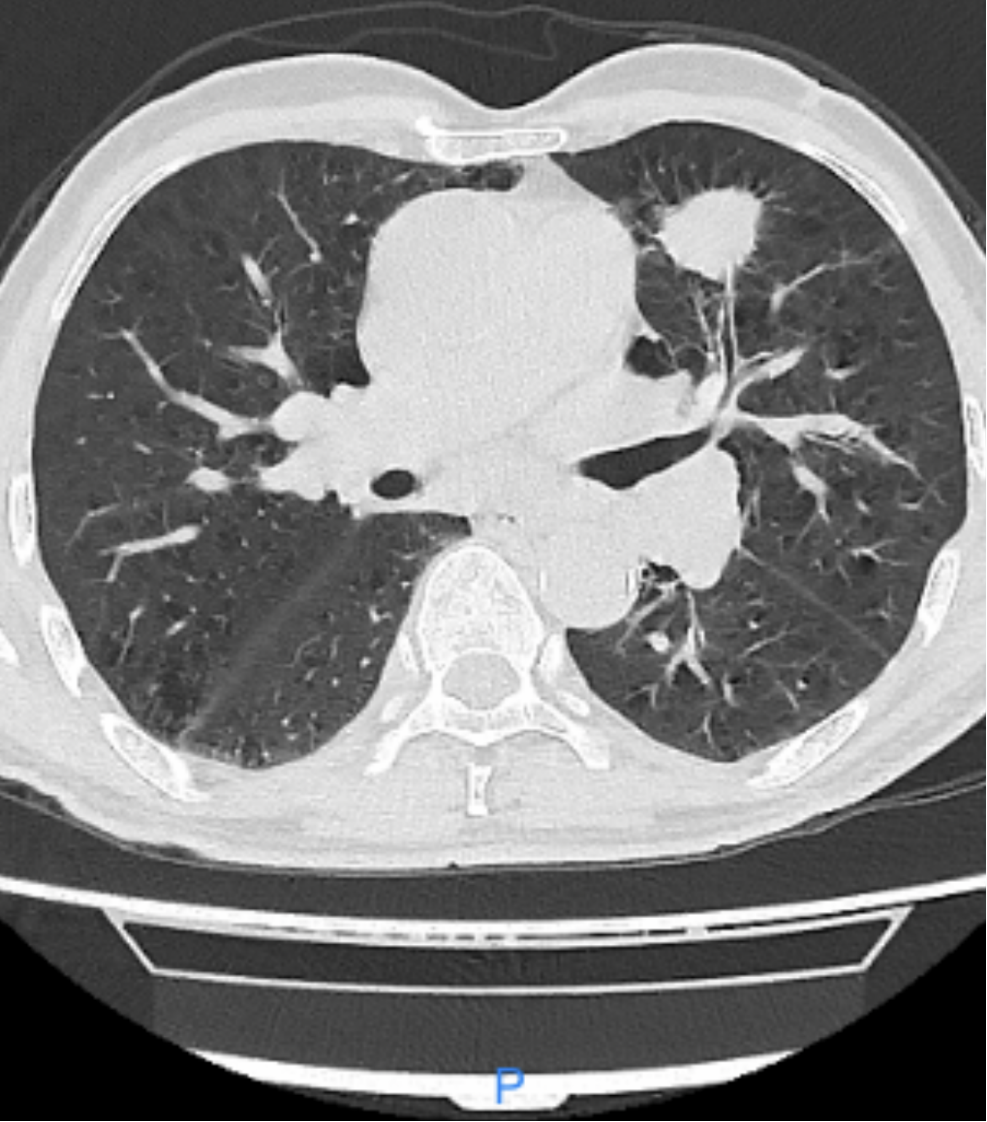

病例二:III期不可切除肺癌免疫轉化手術(shù)病例患(huàn)者,湯xx, 男(nán),63歲,發現肺癌4月餘,要求(qiú)手術治療。查體:生命體征平穩,心、腹(fù)未見明顯異常,胸廓對稱無畸形,雙肺叩診呈清音,聽診呼吸音粗,右上肺可及少許幹(gàn)囉音,餘肺部未聞及幹(gàn)濕囉(luō)音。輔助檢查:胸部CT示左肺上葉肺癌,縱膈及(jí)左肺門淋巴結腫大。入院診斷為左肺上葉腺癌,3.0x3.5 cm, 對(duì)側縱膈淋巴結腫大,T2N3M0 IIIB期腺癌。患(huàn)者經皮肺穿刺病理示:(左肺)考慮(lǜ)浸潤性腺癌。基因檢測無靶點,免疫檢測(cè)PDL-1 95%。從(cóng)2023-6-21到2023-8-24行單藥免疫治療(信迪利單(dān)抗)4個療程後,複查胸部CT示腫瘤明顯縮小,淋(lín)巴節消失,轉化(huà)治(zhì)療成功。患者於2023-9-27在(zài)插管全麻下行單孔胸腔鏡下左上肺葉切除+縱膈(gé)淋巴清掃術。術後病理診斷:(左上肺葉)鏡下見局部肺泡上皮不典型增生(shēng),呈附壁結構(gòu),間質纖維組織增生較明顯,伴(bàn)多量淋巴細(xì)胞、漿細胞及不等量的泡(pào)沫樣細胞、多核巨細胞等浸(jìn)潤,結合臨床可(kě)符合治療後改(gǎi)變,僅見少許附壁生長結構為主的腺癌殘留。新輔(fǔ)助治療後評估:存活腫瘤細胞比例約5%,壞(huài)死比例0%,間質比例(包(bāo)括纖維化及炎症)約95%,炎症反應等級中度,(支氣管斷端(duān))未見癌累及。(第5組淋巴結)5枚,可見纖(xiān)維化(huà)、鈣化等治療後反(fǎn)應,均未見癌轉移(0/5)。(第7組淋巴結)4枚,可(kě)見纖維化等治療後(hòu)反應,均未見癌轉移(yí)(0/4)。腫瘤及淋巴結病理緩解達到MPR。

免疫治療後胸部CT

免疫(yì)治療後(hòu)胸部CT